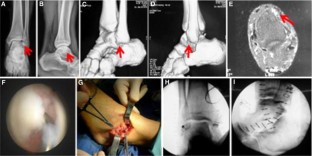

Fig. 2